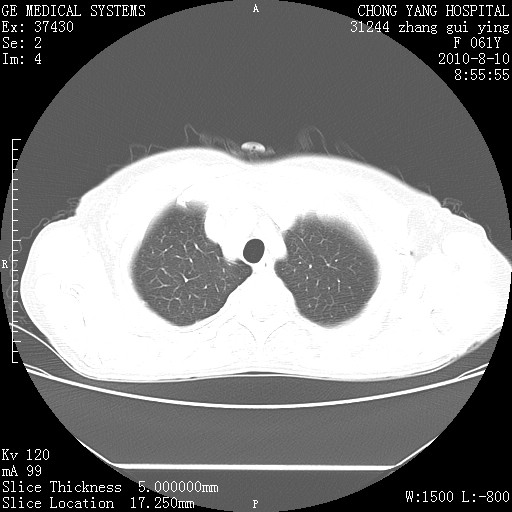

标题: CT28314:F61Y胸部增强,发热咳嗽一周入院,后面的为一周前平 [打印本页]

标题: CT28314:F61Y胸部增强,发热咳嗽一周入院,后面的为一周前平

右肺下叶中心性肺癌可能性大

1、支持考虑右侧中央型肺癌伴右肺中叶节段性不张及下叶支气管黏液痰栓    2、左肺上叶舌段感染。

支持右下肺中央型肺癌并左上肺感染.

双肺感染性病变,不除外合并结核感染。

右肺下叶内基底段近膈不规则肿块,考虑右肺下叶周围型肺癌可能性大。